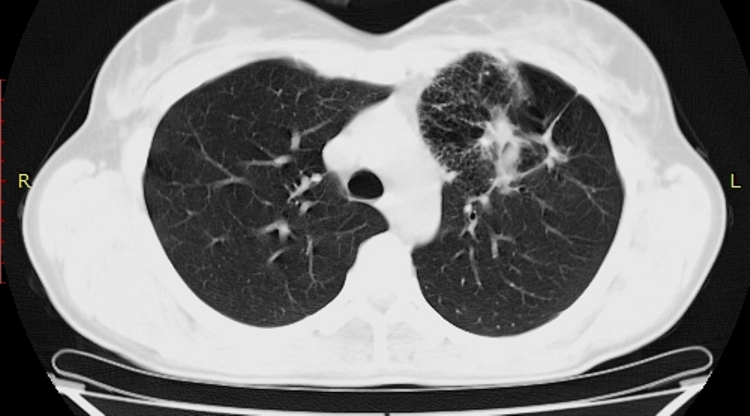

Женщина 35 лет. Жалоб нет. Профилактическая ФГ - дополнительная тень у головки левого корня (снимок пленочный, маленький...не переснимал, так как вряд ли удасться добиться хорошего качества). Подняты пленочные ФГ за 2009 и 2010 гг - есть небольшая деформация легочного рисунка и просветления без четкой контурации у левого корня (естественно - все это ретроспективно, с учетом уже известной информации).

Это НЕ "сотовое легкое"

Отправлять на нормальную КТ с контрастом. Думаю, будет аномалия сосудов, дисгенезия легкого слева. Представленных картинок явно недостаточно, нужны сканы в средостенном окне с контрастом.

Можно подумать  об артерио-венозной мальформации.Тем более имеются характерные изменения в окружающей лёгочной ткани и прилежащих бронхах. Конечно, нужно контрастировать.

Явно аномалия, нет сомнений. Но секвестрация сомнительна, хотя....

Пока, без Дайкома, можно предположить БЭЛ (локальную).

БЭЛ: Буллезная эмфизема легких. Причины: от воспалительных процессов до врожденных ферментативных нарушений.

имхо:скорее всего гипогенезия верхней доли левого лёгкого  с  буллезно-фиброзными проявлениями.